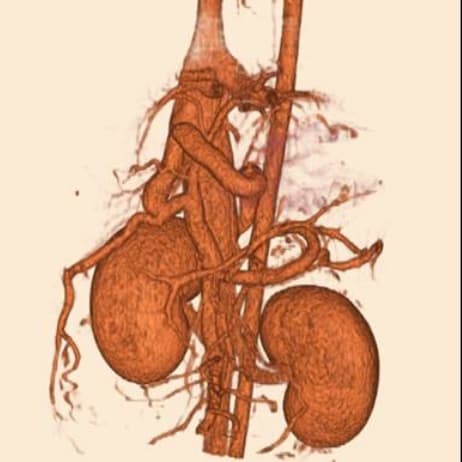

동탄 1 신도시 최초 Aquilion CX/128 slice CT를 동물병원에 도입하였습니다. 최고 사양 CT 모델 Aquilion CX/128 slice를 활용하여 0.5 mm의 얇은 128개의 단면 영상을 신속히 획득 할 수 있어 마취 시간을 단축시킬 수 있습니다. 또한, 128 슬라이스의 고화질의 CT 영상을 통해 영상 왜곡을 최소화하고 X-ray에서는 확인하기 힘든 5 mm 이하의 미세 병변도 확인이 가능하여 정확한 진단을 할 수 있습니다. 심화 진단이 필요한 경우, 조영제 인젝터를 통한 동맥기 촬영으로 종양 유래 확인, 간 질환 진단, 심혈관계 진단이 용이합니다. 저희 동탄시티동물의료센터에서는 본원 환자뿐 아니라 1차 동물 병원과의 CT 촬영 의뢰 시스템을 통해서 원활한 협진이 가능하도록 최선을 다하고 있습니다.

0164 채널 CT 촬영을 통해서 신속하게 고화질 영상을 얻어, 종양 유래 확인 및 전이 평가, 간문맥단락증(PSS), 선천적 뼈 기형과 같은 심화된 진단을 할 수 있습니다.